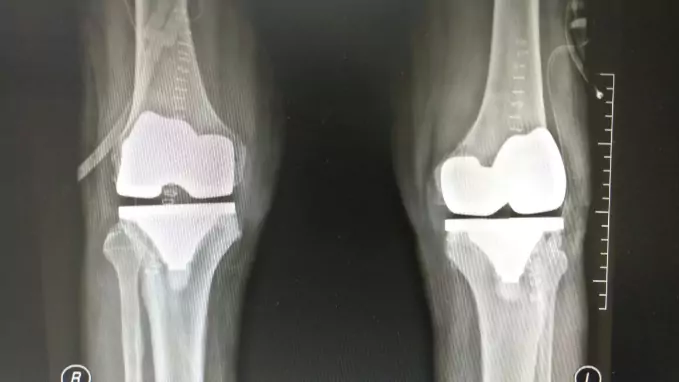

Total Knee Replacement (TKR) Using Stryker Triathlon System

by Dr. Chetan Nagaraj | Apr 8, 2022 | Knee Replacement

Dr Chethan has performed successfully Total Knee Replacement using Stryker Triathlon System A 47-year-old patient had sustained a fracture of his leg bone (tibia) 10 years ago which was treated elsewhere with surgery. Although his fracture had healed, it had healed in...